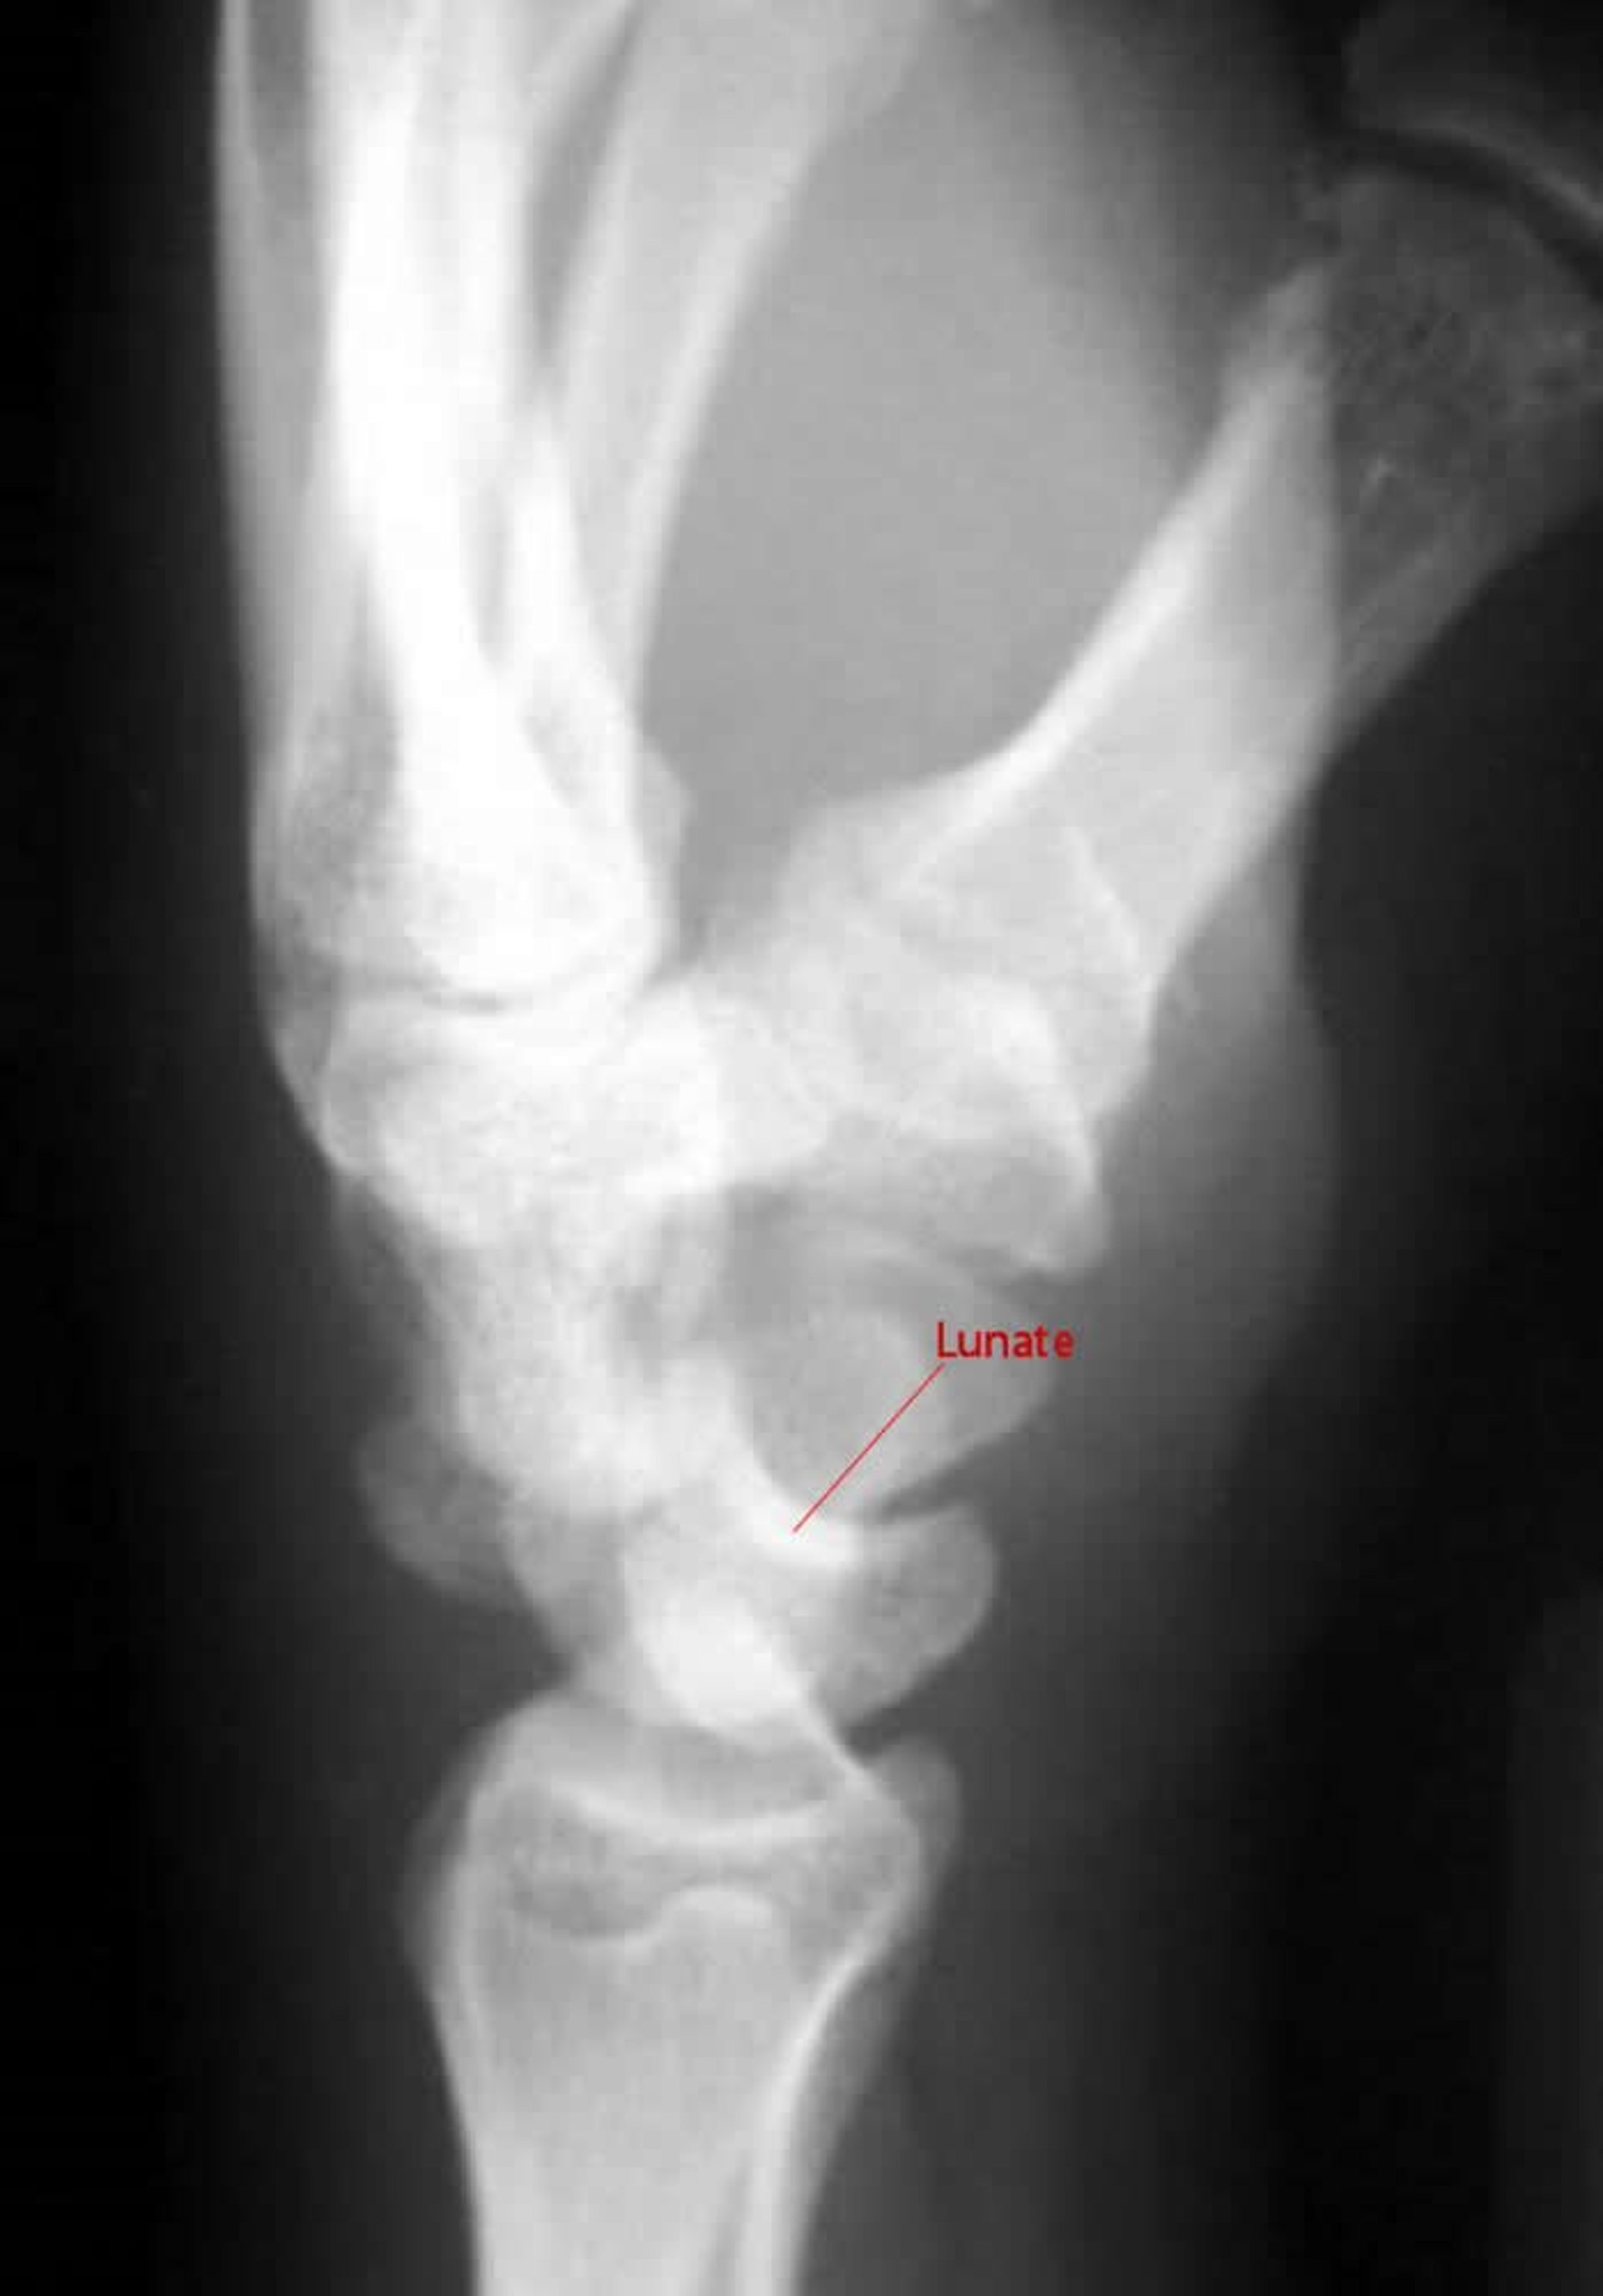

Luxação perilunar

Na incidência lateral de uma luxação perilunar, o capitato não se articula com o semilunar.

Imagem cedida por cortesia de Danielle Campagne, MD.